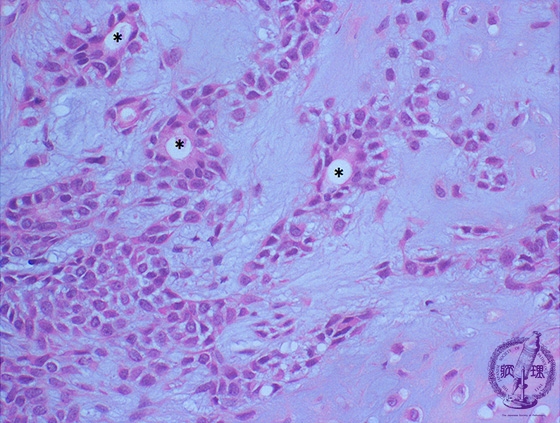

Microscopic finding (HE stain, high-power view):The lumen (*) is lined by glandular epithelial cells, below which are neoplastic myoepithelial cells and a transition to widened intercellular spaces containing mxyoid and chondroid matrices.